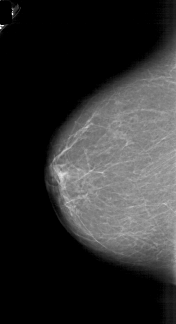

A_1718_1.LEFT_MLO

LEFT_CC LINES 5821 PIXELS_PER_LINE 3166 BITS_PER_PIXEL 12 RESOLUTION 43.5 NON_OVERLAY